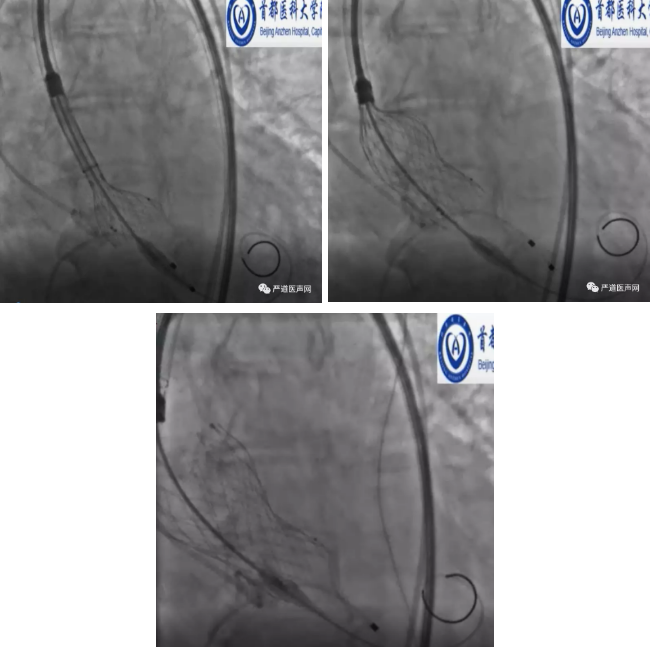

手术有条不紊的进行,采用局部麻醉及镇静。手术第一个难点是导丝的跨瓣建立瓣膜输送的轨道,因为患者流速高,压力阶差大,导丝跨越主动脉瓣膜要面临极大的阻力,但周玉杰教授凭借经验,不到5分钟,导丝跨越瓣膜成功。

轨道建立后,顺利的进行了球囊的扩张,这时到了最关键的时刻,Venus Plus 瓣膜的输送和释放,而恰巧这个时候镜头切向了会场。在国外,术者们对如此高难度手术往往束手无策,所以主持人和现场的观众都兴致饶饶的看着中国专家的场上表现。果然,瓣膜运送的阻力非常大,尤其是通过迂曲的主动脉弓风险更大,周玉杰教授在每一步前进的过程中都要感受到前进所遇到的阻力,除了避免瓣膜损害主动脉弓外,助手也要密切配合,任何一个配合不良的动作,都会增加导丝刺破心脏的风险,此外为保障瓣膜的同轴性,还需要借助一个网篮作为牵引,将瓣膜送至了合适的位置。

这样的操作,对术者的操作技巧和团队的配合要求都是非常高。场内外专家对瓣膜的释放的位置相当满意后。大家屏住呼吸,伴随着刘巍教授手指在输送器按钮上缓慢的移动,瓣膜在慢慢的绽放。此时周玉杰教授的双手承载着压力是巨大的,因为释放的过程要对抗瓣膜血流强大的冲击,只有采用精准的力量才能使瓣膜固定在合适的位置,避免上下移位。就这样,在140次/分的心脏起搏支持下,瓣膜完美绽放到了合适的位置。

瓣膜完美绽放的过程